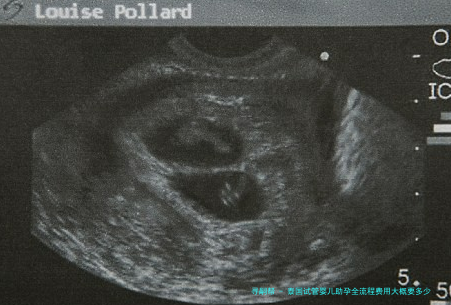

一、前期检查与促排卵阶段:初步评估与卵泡生长

二、取卵与胚胎培养阶段:核心技术与培育过程